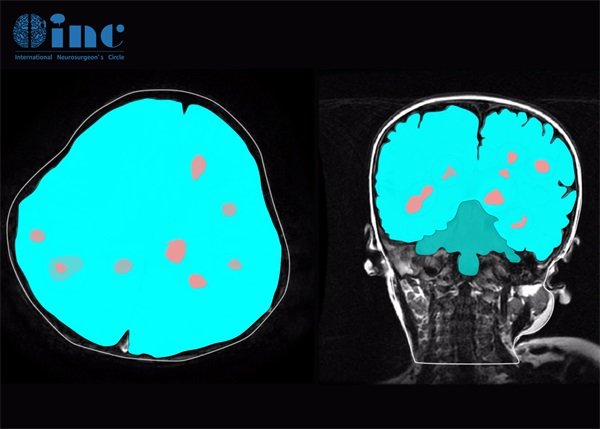

在MRI影像上,脑海绵状血管瘤通常表现为高信号或混合信号病变。它们的边缘常常是模糊的,且肿瘤内部可以看到多发的腔隙,这些腔隙是由血液滞留和微血管扩张导致的。相较于脑实质,其信号强度会有所不同。

在进行对比增强扫描时,脑海绵状血管瘤的表现可能较为复杂。通常情况下,这类病变的增强效果较弱,可能仅在边缘观察到微弱增强,但内部的腔隙则并不明显显示增强。

除了MRI表现,CT扫描也可以用来监测脑海绵状血管瘤。在CT下,这些病变呈现为低密度区,可能伴有轻度的脑水肿。此外,病变在额叶或颞叶多个位置均有可能出现,这使得其临床表现各异。